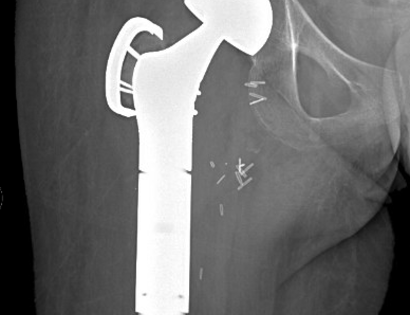

This is an x-ray of a patient after the surgical placement of the prosthesis and removal of upper femur.